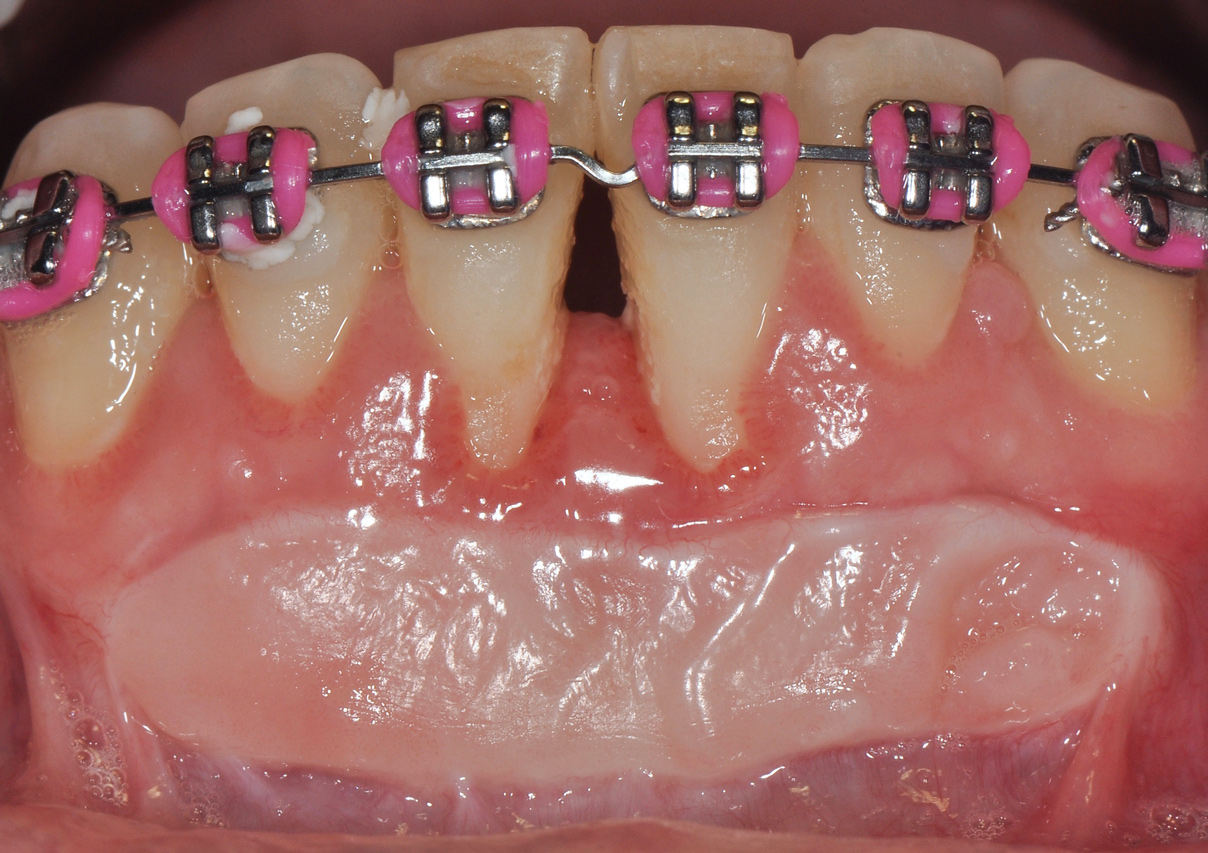

Although similar to the root coverage procedures mentioned above, gingival augmentation procedures not aimed at achieving root coverage are performed to facilitate plaque control, improve patient comfort, and prevent future periodontal recession. They may be used in conjunction with restorative, orthodontic, or prosthetic dentistry. The consensus report from the AAP's workshop group on soft-tissue non-root coverage procedures concluded that a specific minimum amount of keratinized tissue is not needed to prevent attachment loss when optimal plaque control is present; however, if plaque control is suboptimal, a minimum of 2 mm of keratinized tissue is needed. 12 A standard procedure that is recognized to predictably gain keratinized tissue is the use of an autogenous gingival graft.12 Figure 5 through Figure 8 demonstrate the healing progression of a patient with poor oral hygiene whose mucogingival defect was treated with a free gingival graft and L-PRF from the patient's own blood.

(5.) Pretreatment photo of patient with recession to be treated with a free gingival graft (harvested from the palate) and L-PRF.

Figure 5

(7.) Postoperative view of the graft recipient site after 3 weeks showing healing progress with poor oral hygiene.

Figure 7